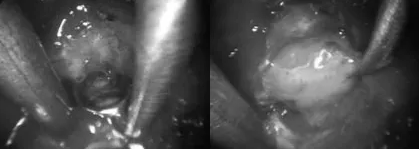

第二阶段,通过右侧眉毛切口,切除了位于垂体区域右侧的肿瘤部分。术中协同采用显微镜与神经内镜,前者提供立体视野,后者则深入术野盲区,通过双镜联合技术,减少了脑组织的牵拉,精准分离了黏连的肿瘤组织。

内镜下的成像清晰地显示了在真空吸引和刮匙工具的配合下,肿瘤被逐步切除的过程。在该过程中,可以观察到典型的白色、易于溶解的垂体组织。